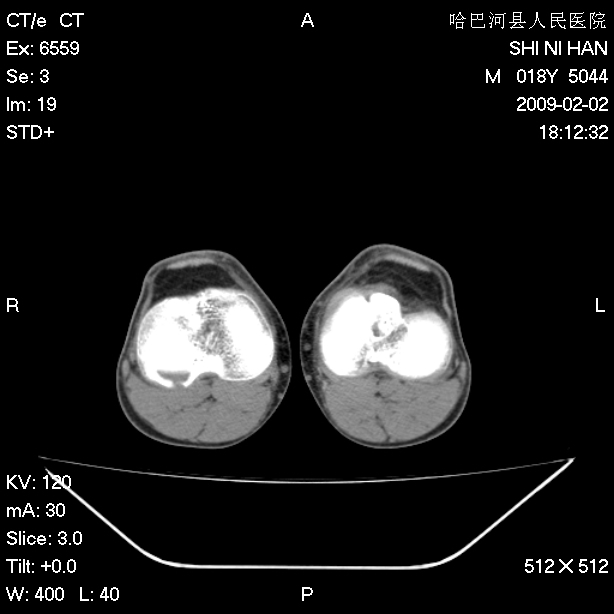

标题: CT17889:外伤后右膝关节反复疼痛3年余 [打印本页]

标题: CT17889:外伤后右膝关节反复疼痛3年余

ct未见明显异常。关节腔未见明显积液,半月板未见明显撕裂。但最好还是mri看看韧带及半月板情况。